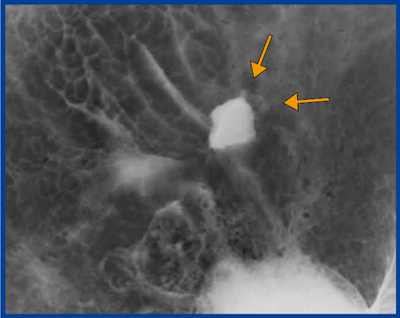

図1は,撮影中に技師が透視画像で微小がんに気づき,追加撮影を行った画像である。図1では,前庭部前壁に微小胃がんが認められる。びらんのようにも見えるが,棘状で外に広がるようなspicular formation cancerが明瞭に描出されている。

図1 X線検査の追加撮影により診断された |